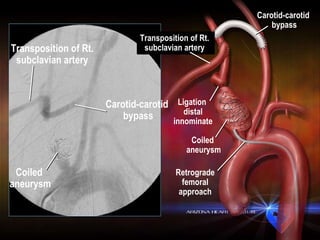

Coiled  aneurysm Transposition of Rt.  subclavian artery  Carotid-carotid  bypass Coiled  aneurysm Transposition of Rt.  subclavian artery  Carotid-carotid  bypass Ligation  distal innominate Retrograde femoral approach

Expanding ascending aneurysm Dissection False lumen True lumen Previous ascending graft for type I dissection